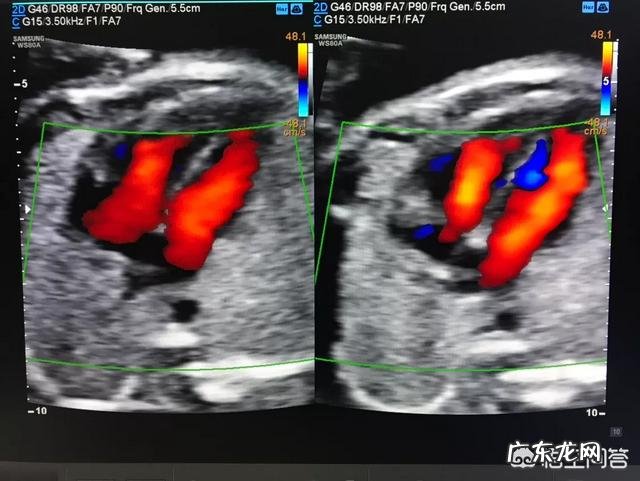

一般在妊娠18-24周左右的时候可以做彩超产前排畸,通常孕妇在怀孕20周去医院进行检查,最好不要超过孕28周 。因为胎儿在24周左右时正是大脑突飞猛进的发育时期,这个时期的胎儿的结构已经形成、胎儿的大小和羊水适中,在宫内活动空间很大,胎儿骨骼回声影响小,图像也比较清晰 。

四维彩超什么时候做最好?一般是在怀孕24周-28周是做四维彩超的最佳时间,因为胎儿在24周左右是胎儿大脑突多猛进的发育时期,这个时期胎儿的结构已经形成,胎儿大小以及羊水适中,在宫内活动空间较大,胎儿骨骼回声影响较比小,图面清晰度比较高 。

四维彩超可以从多个方位和多角度来观察胎儿,进而直观地反映出胎儿真实生长以及发育的情况,能够很好地排除先天性畸形、先天性心脏病等婴儿的降生,因此在一系列的产期检查当中,四维彩超检查是必不可少的一项 。千万不要觉得这些检查都是可有可无的自己随便应付一下就可以了,实际上如果忽略了四维彩超检查出现了问题,那真的是会影响宝宝一生的 。